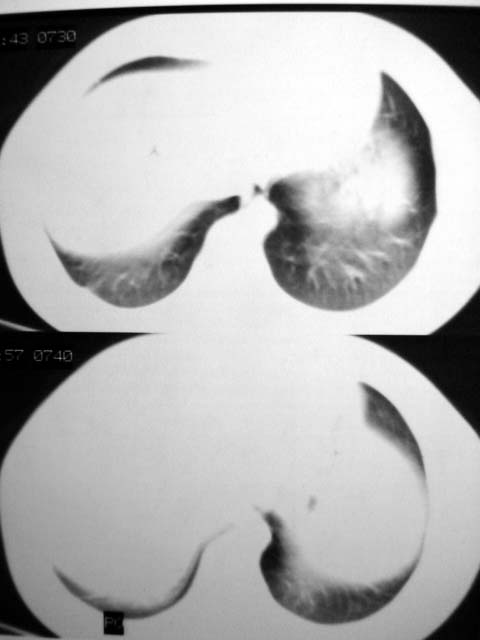

标题: CT12463:女,19岁,炎性假瘤?结核球? [打印本页]

标题: CT12463:女,19岁,炎性假瘤?结核球?

女,19岁,体检时发现。炎性假瘤?结核球?

早产儿,幼时体弱,常感冒肺部感染,13岁后好转。两月前“感冒”后咳嗽两周。

纵隔窗肿块明显较肺窗小,切粗长毛刺,“倒核桃”征:考虑炎性假瘤

病灶肺纵比较大,边缘平直,周围无卫星灶,考虑炎症。建议抗炎治疗后复查。

病灶片状改变,呈钱币样,周围炎性反应明显,考虑球形肺炎可能性大,球形肺炎与炎性假瘤鉴别的重要一点是,炎性假瘤抗炎治疗不会明显改变。

首先要说ct机太差,片子质量不佳,一定是2秒以上机器的作品!其次ct技师需进一步培训,象这种情况就应该针对病灶部位做薄层或高分辨扫描。不过从上传影像看,患者年轻、病灶周围没卫星灶倒支持炎性假瘤诊断,不过象这种部位也有可能是叶间包裹性积液可能。只是ct机太、太差,很难诊断,如一秒机扫描出来90%可直接诊断,有必要时可结合矢状位三维重建。所以要我说建议患者在亚秒(至少是1秒)机上重扫十分有利于正确诊断。

考虑炎症,抗炎后复查。理由:病变肺窗显示的大小明显大于纵隔窗,提示病变周围为密度偏低的渗出改变。不同于结核球和肿瘤。